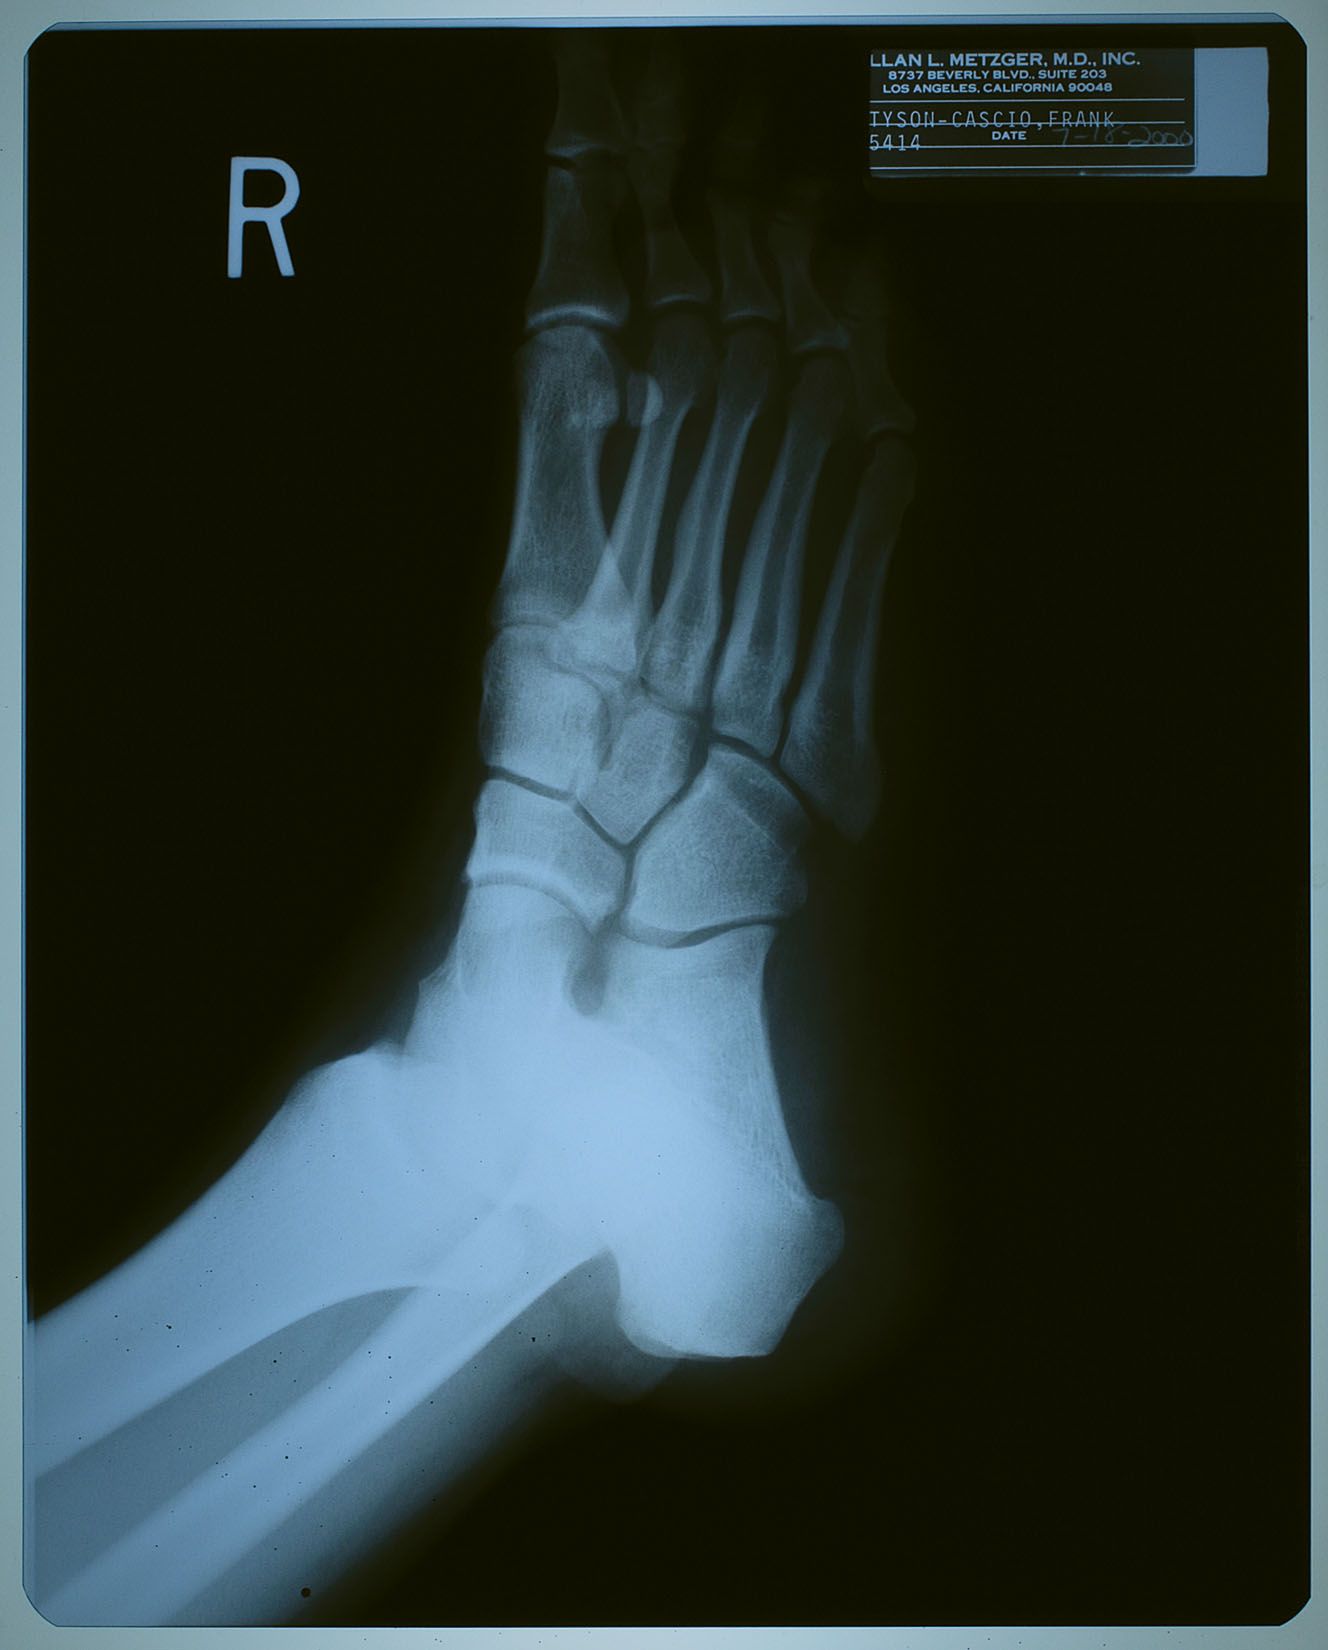

2000年7月18日、ネバーランドで子供たちと遊んでいて

怪我をした時に撮ったX線写真。

名前が 「タイソン-カシオ,フランク」 になっているけども、

カシオ本を読んだ御仁はお判りでしょう。

"タイソン" というのは、前年からマイケルの代理人を務めるようになった

フランク・カシオ君の仕事上での通名。

診療所などでは、マイケルがプライバシー面からフランク君の名を使う事もあったそう。